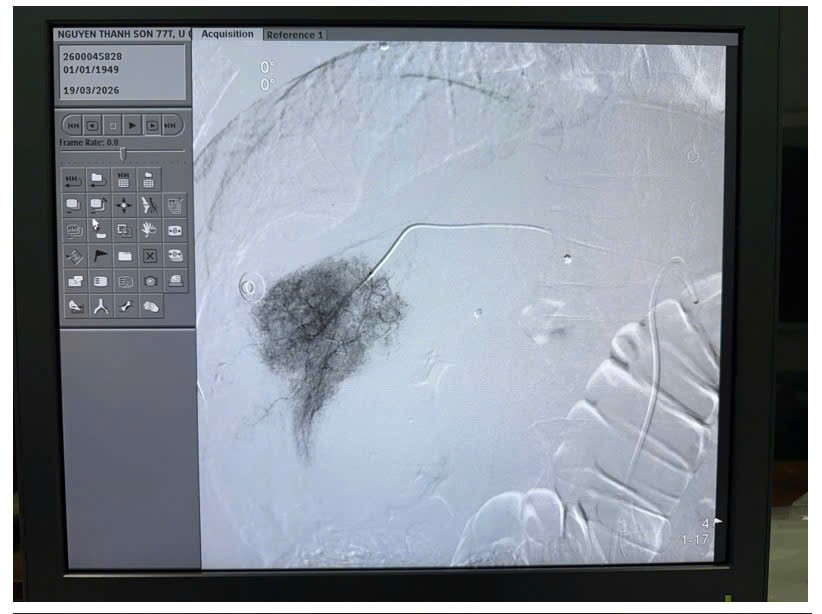

Sau hội chẩn liên chuyên khoa, ê-kíp

quyết định lựa chọn phương pháp can thiệp nội mạch – nút mạch hóa chất (TACE)

nhằm cầm máu và kiểm soát khối u. Dưới hướng dẫn của hệ thống chụp mạch số hóa

xóa nền (DSA), các bác sĩ tiến hành chọn lọc động mạch nuôi khối u và thực hiện

nút mạch bằng vật liệu chuyên dụng kết hợp hóa chất. Kết quả can thiệp đạt hiệu

quả cao, làm tắc khoảng 90% hệ thống mạch máu nuôi khối u, kiểm soát tốt tình

trạng chảy máu.